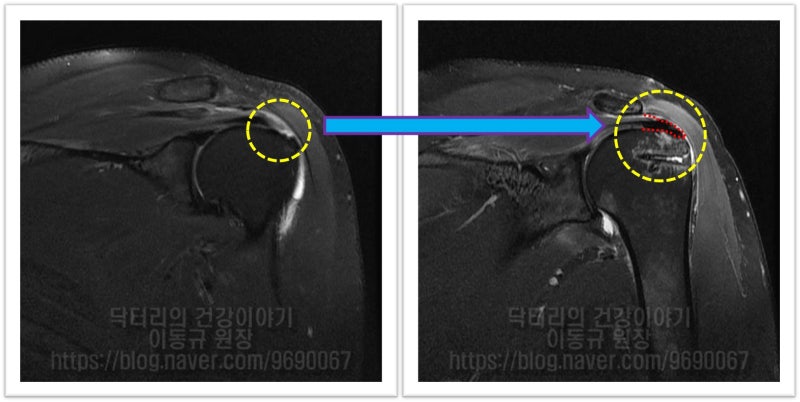

MRI 상 파열 사이즈도 크지 않고 힘줄 상태로 그렇게 나쁘게 보이지 않습니다. 관절경을 통하여 봉합술을 하기로 하였습니다.

이 환자의 경우 나이가 비교적 젊음에도 불구하고 힘줄의 상태가 매우 좋지 않았습니다. 아마 수년간 통증주사(아마도 스테로이드)만 맞고 팔을 계속 사용하면서 회전근개 손상은 점점 진행되고 퇴행성 변화가 가속화 된 것으로 사료됩니다. 수술 후 6주에 MRI 검사를 시행하였습니다.